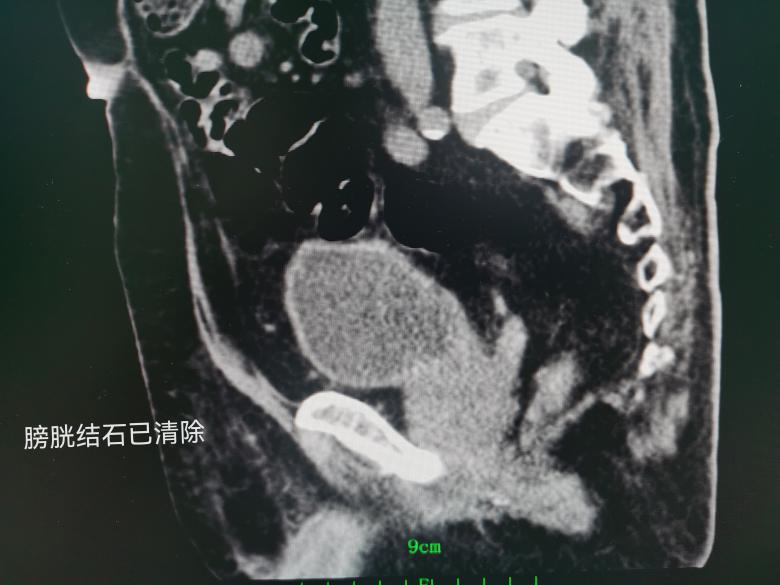

林爷爷(化名)是一名98岁的高龄患者,因反复尿痛、肉眼血尿、十余年排尿困难来医院就诊,经检查发现膀胱内有两枚7CM“鹅卵石”样的结石,占据了整个膀胱的空间。不仅如此,左侧输尿管下段也藏有两枚小结石。

手术由泌尿外科学科带头人谢群主任医师亲自主刀,采用pilipili 新引进的大功率钬激光经尿道粉碎结石,由于结石较大,手术历时3小时,术中几乎无出血,在麻醉科的精心管理下,患者顺利渡过手术难关,目前已平安出院。